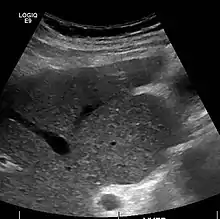

Caudate lobe hypertrophy on ultrasound due to cirrhosis

The diagnosis of cirrhosis in an individual is based on multiple factors.[22] Cirrhosis may be suspected from laboratory findings, physical exam, and the person's medical history. Imaging is generally obtained to evaluate the liver.[22] A liver biopsy will confirm the diagnosis; however, is generally not required.[35]

Imaging

Ultrasound is routinely used in the evaluation of cirrhosis.[35] It may show a small and shrunken liver in advanced disease. On ultrasound, there is increased echogenicity with irregular appearing areas.[52] Other suggestive findings are an enlarged caudate lobe, widening of the fissures and enlargement of the spleen.[53] An enlarged spleen, which normally measures less than 11–12 cm (4.3–4.7 in) in adults, may suggest underlying portal hypertension.[54] Ultrasound may also screen for hepatocellular carcinoma and portal hypertension.[35] This is done by assessing flow in the hepatic vein.[55] An increased portal vein pulsatility may be seen. However, this may be a sign of elevated right atrial pressure.[56] Portal vein pulsatility are usually measured by a pulsatility indices (PI).[55] A number above a certain values indicates cirrhosis (see table below).